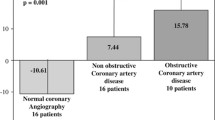

There was strong inverse correlation between ADI and CAC (r 2 = −0.69, P = 0.0001). ADI decreased proportionally from CAC 0 to CAC 1–100 to CAC 101–400 to CAC 400+ in both genders (Fig. 3a and b). Furthermore, severity of CAC increased incrementally in each FRS category as ADI decreased; similarly, in each ADI category as FRS increased. The highest CAC was noted with the combination of the lowest tertile of ADI and FRS 20%+; The lowest ADI was observed in subjects with highest CAC and FRS (Fig. 3b). ADI decreased with the severity of metabolic status in each CAC category in which diabetics with CAC 400+ had the least ADI. (Figure 3c) After adjustment for age, gender, conventional cardiac risk factors, and FRS by relative risk regression analyses, the risk of each standard deviation decrease in ADI was 1.66 for CAC 1–100, 2.26 for CAC 101–400 and 2.32 for CAC 400+ as compared to CAC 0. (Table 2) Multivariate regression analysis showed that ADI was an independent predictor of the severity of CAC.

Increasing severity of CAD was associated with increase in CAC and FRS, and decrease in ADI (Table 1). After adjustment for age, gender, conventional cardiac risk factors, and CAC, ADI was independent predictor of significant CAD. (Table 3).